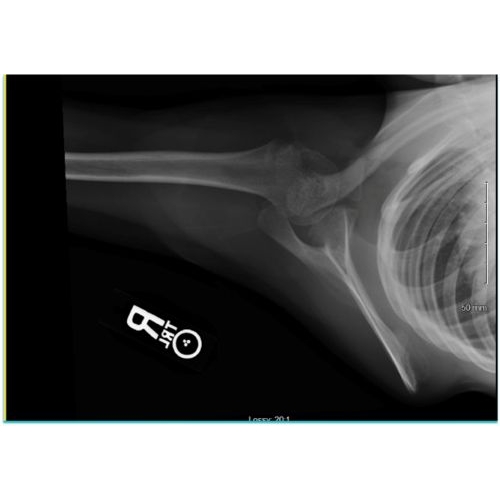

At six weeks, the patient demonstrated full pain free range of motion, symmetric strength bilaterally, including scapular protraction, with no evidence of scapular winging. Repeat x-rays demonstrated bony callus formation at the fracture site, and evidence of resorption of the cartilage fragment Case Photo #7 , Case Photo #8 . Follow up was scheduled for 12 months to confirm appropriate bony healing.